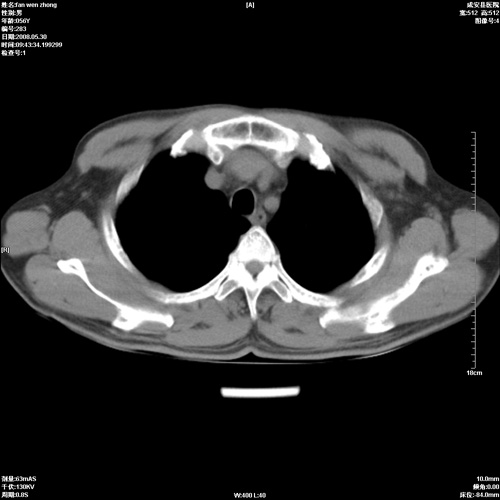

病人 男 56岁 一周前高热,体温达39-40度,经抗炎治疗后,体温渐降,达37,5-38度,轻微咳嗽,胸部不适 查白细胞为1.3万 行ct检查,请分析。

双肺内可见多发结节状病灶,并见小空洞,病人高热,白血球增高,应该是典型的迁徙性肺脓肿(多为金黄色葡萄球菌感染)。查一下口腔等其它部位有无感染灶。

双肺内可见多发结节状病灶,并见小空洞,病人高热,白血球增高,应该是典型的迁徙性肺脓肿(多为金黄色葡萄球菌感染)。建议治疗后复查.